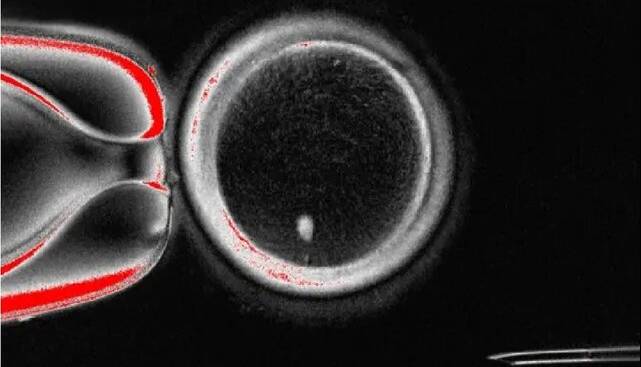

آنها هسته یک سلول پوست را به یک تخمک اهدایی که هسته آن جدا شده بود، پیوند زدند. سیتوپلاسم تخمک اهدایی باعث شد هسته سلول پوست نیمی از کروموزوم‌های خود را دور بریزد و «میوز» را تقلید کند.

نتیجه، یک تخمک هاپلوئید بود که می‌توانست از طریق لقاح مصنوعی(IVF) استاندارد با اسپرم لقاح داده شود و جنین‌هایی با ورودی ژنتیکی برابر از هر دو والدین تشکیل دهد.

محققان در این مطالعه، 82 تخمک عملکردی تولید کردند و آنها را با اسپرم لقاح دادند. در حالی که اکثر آنها در مرحله 4 تا 8 سلولی به دلیل ناهنجاری‌های کروموزومی متوقف شدند، حدود 9 درصد روز پس از لقاح به مرحله بلاستوسیست رسیدند.